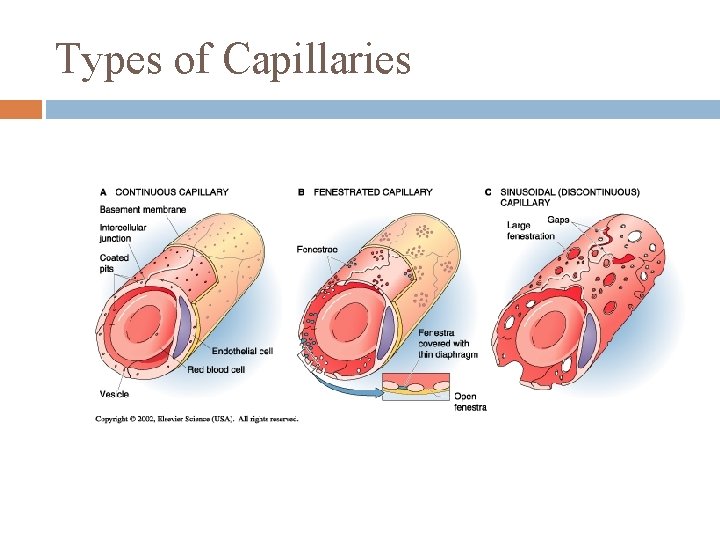

Types of Capillaries